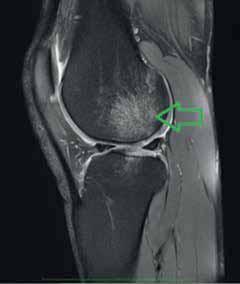

Rycina 4.1. Podchrzęstne ognisko obrzęku szpiku w zakresie kłykcia bocznego kości udowej (strzałki)

Rycina 4.2. Hiperintensywny obszar uszkodzenia chrząstki stawowej w zakresie MFC – kłykcia przyśrodkowego k. udowej (strzałka)